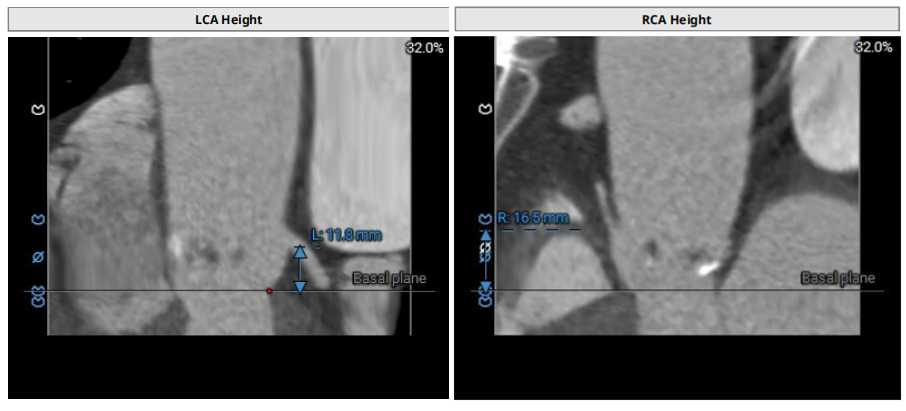

患者男性,77岁,三叶瓣。主动脉瓣重度狭窄,术前平均跨瓣压差48mmHg,峰值流速4.6m/s。瓣环及瓣叶钙化,瓣环面积径23.4mm。左冠高度11.8mm,右冠高度16.5mm。外周入路未见明显钙化,内径尚可。

术前评估